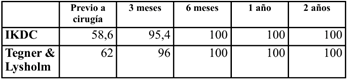

Tabla 1. Score de Tegner & Lysholm. Valora la capacidad funcional de la rodilla. Va de 0 a 100 puntos, pudiendo el resultado ser pobre (<65 puntos), aceptable (65-83), bueno (84-90) o excelente (>90)

Tabla 2. Score de IKDC (International Knee Documentation Committee). Valora 3 grandes elementos: síntomas, actividad deportiva y función/actividades de la vida diaria (AVD). Va de 0 a 100 puntos.

Tabla 2. (continuación) Score de IKDC (International Knee Documentation Committee). Valora 3 grandes elementos: síntomas, actividad deportiva y función/actividades de la vida diaria (AVD). Va de 0 a 100 puntos

Se proscribió el apoyo por 6 semanas, y se comenzó con tratamiento fisioterápico precoz. Se volvieron a realizar los scores IKDC, Tegner & Lysholm a los 3 y 6 meses, al año y a los 2 años posterior a la cirugía (Tabla 3). Además a los 6 meses, se solicitó una nueva RNM para control imagenológico de la reconstrucción del LCA y de la reparación meniscal (Figura 4). A los dos años del seguimiento clínico, se solicitó una goniometría de miembros inferiores para descartar desaxaciones o dismetrías debidas a una lesión fisaria (Figura 5). No se evidenciaron complicaciones de la herida, ni re-rotura del LCA, ni falla de la sutura meniscal, ni artrofibrosis de dicha rodilla.

Tabla 3. Scores funcionales IKDC, y Tegner- Lysholm previo a la cirugía, a los 3 y 6 meses, al año, y a los 2 años posterior a la misma.